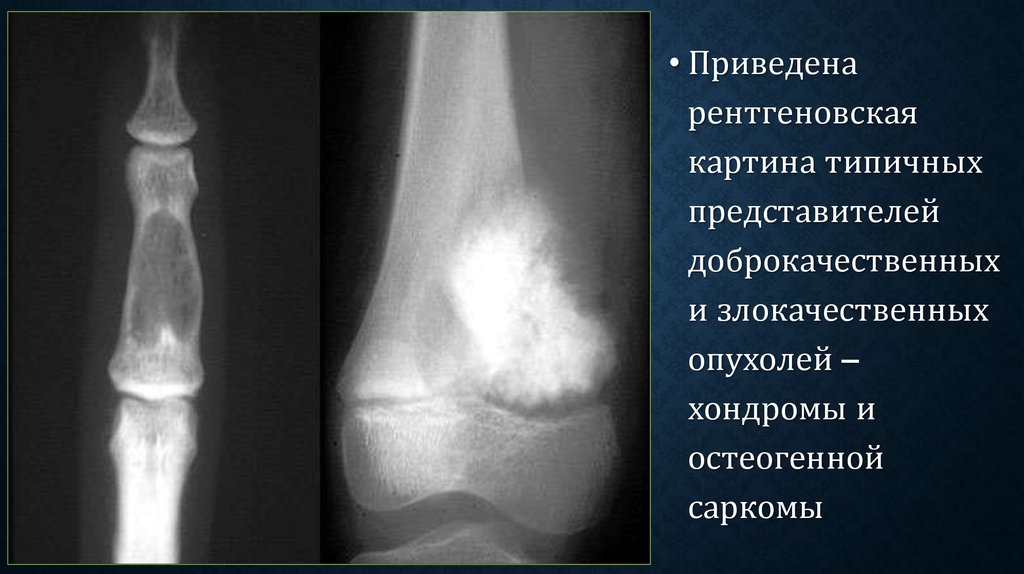

Рентгенологическая картина остеогенной саркомы кости - 98 фото